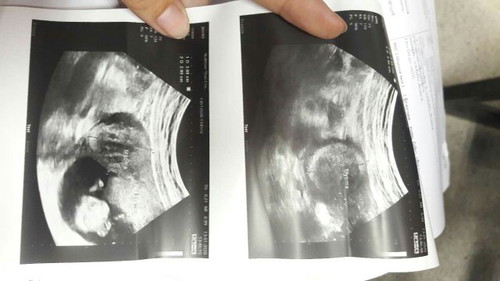

ขอสอบถามแม่ๆหน่อยคะ (ท้อง 2 13w+5 แล้วคะ) ??แม่ๆทานไหน มีประสบการณ์ตอนท้องแล้วเจอก่อนเนื้อ หรือเนื้องอกในมดลูกตอนท้องบ้างคะ อันตรายไหมคะ มันหายไปเองรึเปล่า ถ้าไม่หายคุณหมอทำอย่างไร ลูกคลอดมาแข็งแรง ปลอดภัยไหมคะ แอบกังวลแล้วคะ ▶️เราฝากท้องกับ รพ.รัฐ เราซาวด์ครั้งแรกตอนท้อง 8w หมอแจ้งว่าเรามีก้อนเนื้อ หรือเนื้องอกในมดลูก ซึ้งเราไม่รู้มาก่อนเพราะก่อนท้องเรามีประจำเดือนมาปกติ ไม่ปวดท้อง ท้องไม่โต ปกติทุกอย่างคะ เราถามหมอว่าจะอันตรายไหม หมอไม่ได้ตอบว่าอันตรายรึเปล่า แต่หมอบอกว่าต้องดูตามอายุครรถ์ ว่าเนื้องอกนี้จะใหญ่ขึ้นหรือเปล่า #ขอบคุณแม่ๆนะคะ